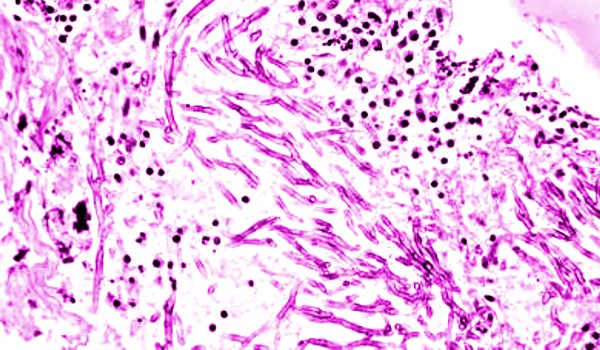

MİKOZİS deride mantarsı urların gelişmesiyle ortaya çıkan hastalık. Çoğu zaman öldürücü olan mikozis, genel ve süreğen bir hastalıktır; nedeni belli değildir, ancak lösemilere çok benzer.

Ortada herhangi bir lezyon yokken inatçı kaşıntılarla, sedef hastalığını andıran pullar ve egzamaya benzer yaralar ya da yaygın kırmızı bir döküntü ile başlar; bundan sonra urlar belirir; urlar ülserleşebilir ve baş kadar büyüyebilir.

Bu urlar birdenbire ortaya çıkabilir ve yine kendiliğinden kaybolabilir. Lenf düğümleri her zaman şişkindir. Hastalık, yıllarca (10-20 yıl) sürebilir; sonunda hasta zayıflayarak kaşeksi durumunda ölür. Mikozisin tedavisi radyoterapi ve radyoaktif izotoplarla yapılır.